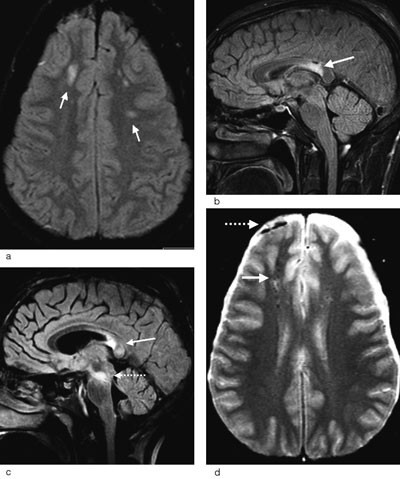

Bildediagnostikk med CT

Ved hodeskader vil CT-undersøkelse av hjernen være førstevalg siden undersøkelsen i akuttfasen er en rask og effektiv teknikk for å påvise frakturer, blødninger og ødem (25). Funn ved cerebral CT hos pasienter med skjærende skade ble først beskrevet i slutten av 1970-årene (9). Pasientene hadde alvorlig klinisk status, men CT viste likevel ikke en signifikant intrakranial blødning som kunne forklare bevisstløsheten. Typiske CT-funn ved diffus aksonal skade er små, punktformede blødninger i overgangen mellom grå og hvit substans i storhjernen og sjeldnere i corpus callosum, blod i ventrikkelsystemet og blod i subaraknoidalrommet rundt mesencephalon (fig 1) (10, 17, 20, 26). Ikke-hemoragiske lesjoner er vanskelige å påvise ved CT (25). CT vil derfor undervurdere forekomst og omfang av den diffuse aksonale skaden. Pasienter med slik skade kan ha normal CT (18). I senfasen vil CT i de mest alvorlige tilfellene kunne vise atrofi med økt ventrikkelstørrelse (9).

Diffus aksonal skade er ikke nødvendigvis diffus i sin utbredelse. Tvert imot forekommer disse lesjonene med et ganske typisk distribusjonsmønster. De fleste lesjoner er små (5 – 15 mm) og lokalisert til hvit substans og overgangen mellom grå og hvit substans i frontallappene og temporallappene (fig 2a). Ved kraftigere traumer kan det i tillegg påvises lesjoner i corpus callosum og i hjernestammen (fig 2b og c). Avhengig av hvilke strukturer som er omfattet av skaden, kan diffus aksonal skade graderes i grad 1 – 3 (tab 2) (25).

| Eventuelt i øvre cerebellare pedunkler |

Lesjonene er vanligvis multiple, ofte så mange som 15 – 20, og kan deles i hemoragiske og ikke-hemoragiske (25, 27). De ikke-hemoragiske lesjonene som forekommer hyppigst, representerer ødem i hjernevevet, mens de hemoragiske skadene trolig skyldes lekkasje av blod fra små kar som forløper langs aksonene og som rives over ved traumet. Blødningene er typisk punktformede, og de minste betegnes gjerne mikroblødninger (fig 2d).

MR-teknikker ved diffus aksonal skade

Hurtige T2-vektede spinnekkosekvenser og FLAIR-sekvenser er MR-teknikker som er følsomme for å påvise endringer i hjernens vanninnhold, og økt vanninnhold vises som områder med høyt signal. Ved FLAIR-sekvensen blir signalet fra det frie vannet i cerebrospinalvæsken undertrykket, og dette øker sensitiviteten for å oppdage ødem i hjernevevet ved diffus aksonal skade (fig 2a og c) (28).

Gradientekko T2*-vektede bilder (såkalt hemosekvens) er velegnet for å påvise blodnedbrytingsprodukter, og lesjoner med blodprodukter fremtrer som signaltomme områder (fig 2d) (25). Størrelsen på disse områdene er betydelig større enn selve blodansamlingen. Dette skyldes at de paramagnetiske blodproduktene forstyrrer magnetfeltet i et større område. Mens lesjonene forårsaket av ødem kan forsvinne etter dager eller uker, vil lesjonene som er forårsaket av mikroblødninger kunne bestå i måneder til år da nedbrytingsproduktene innleires i hjernevevet (14, 25).